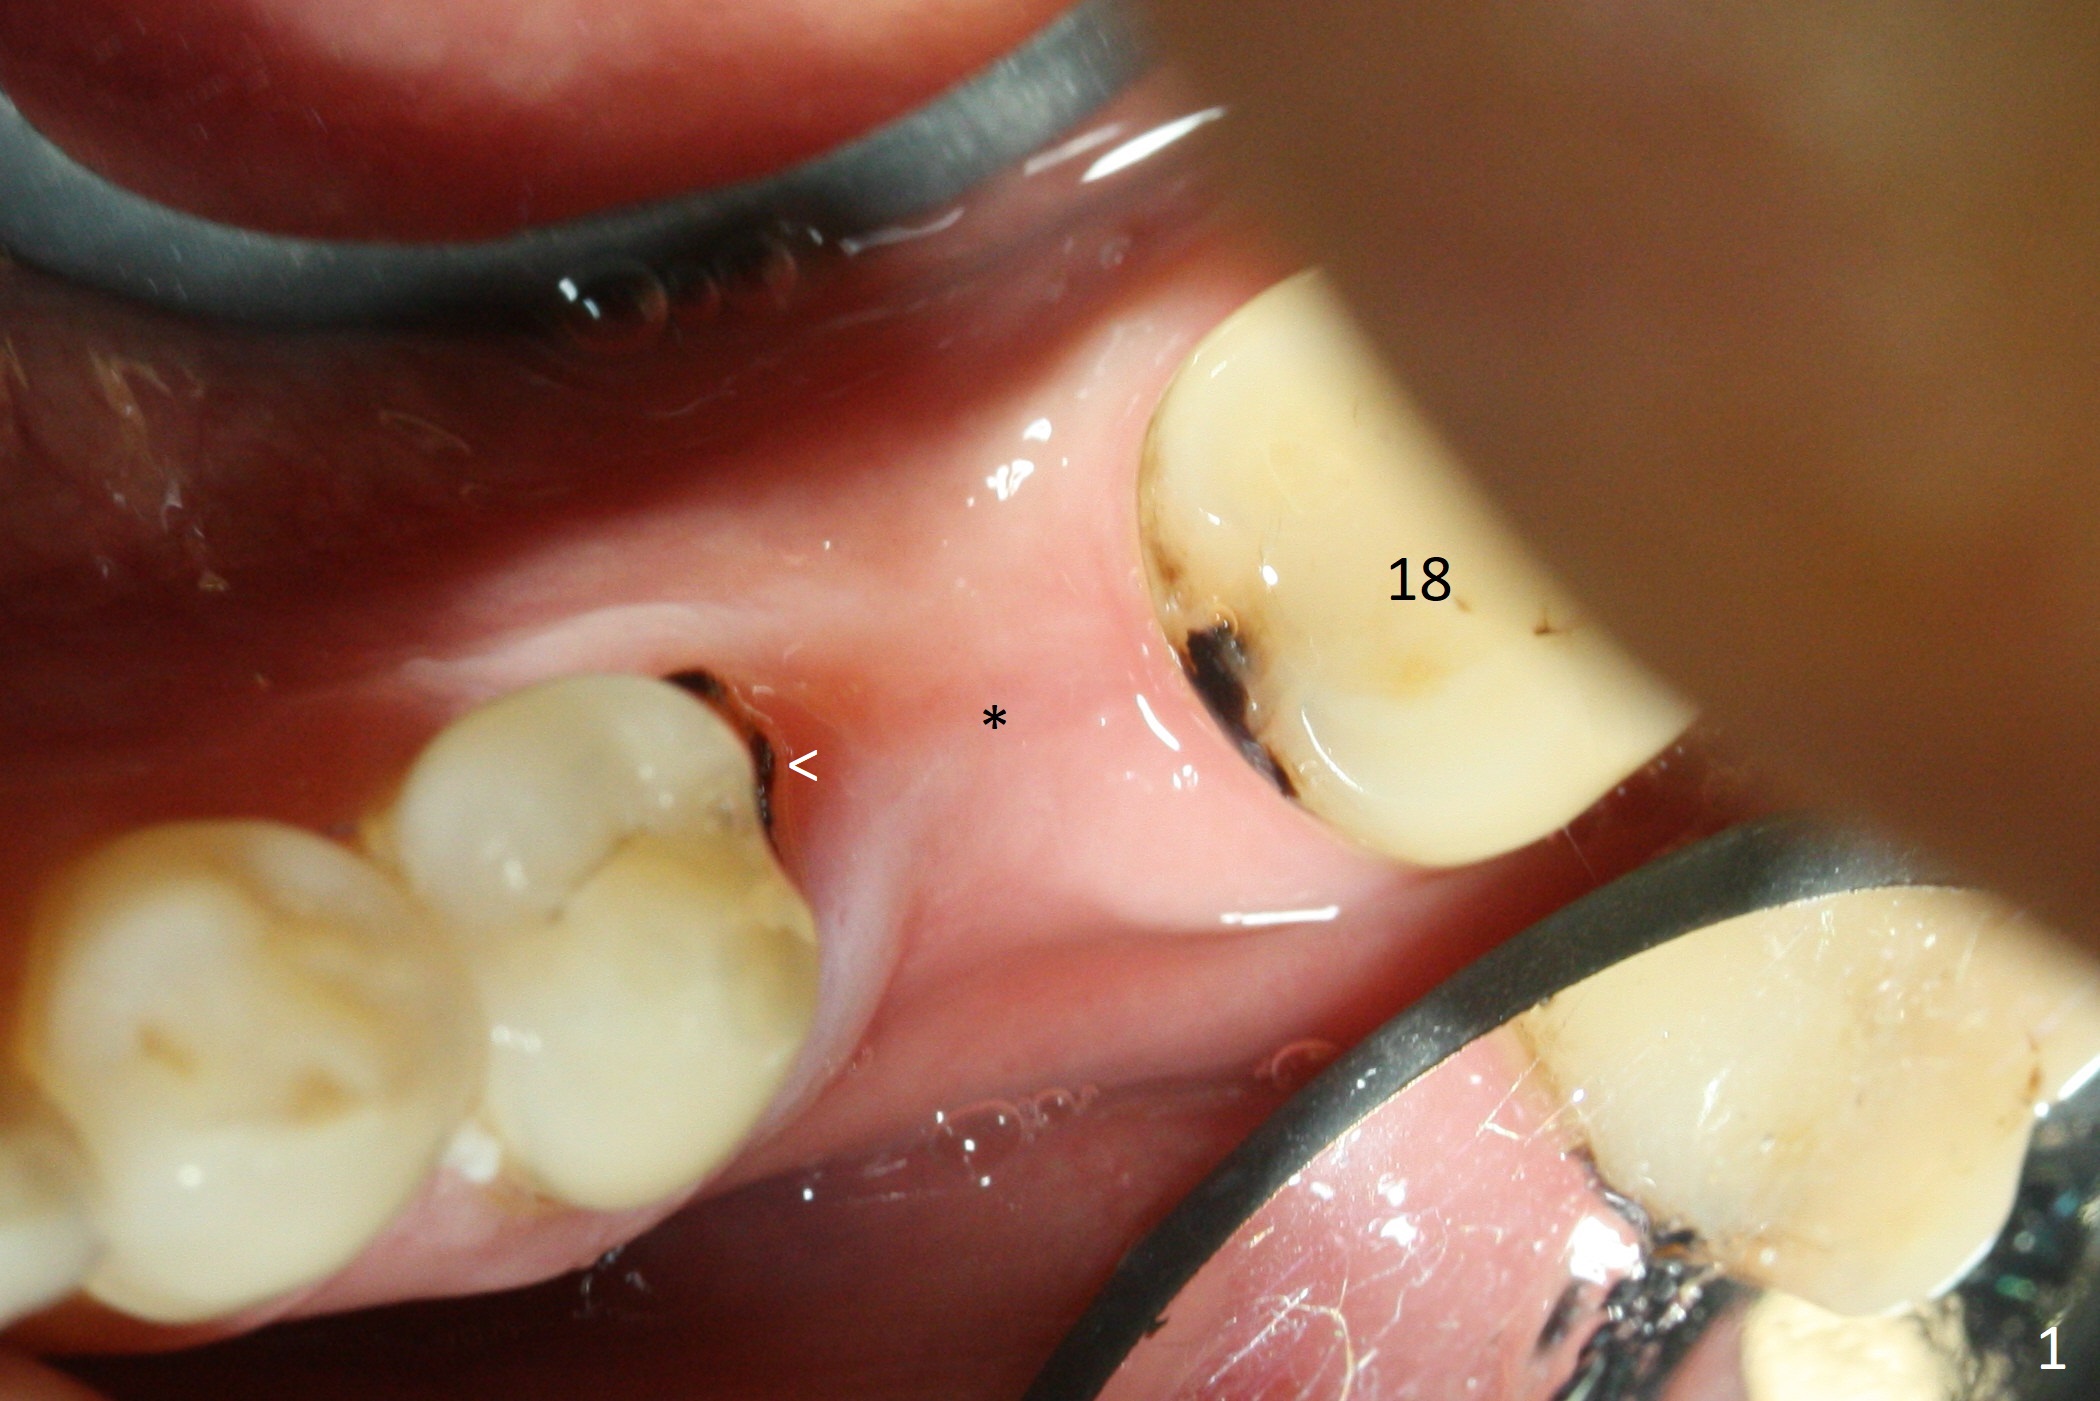

While the mesial ridge is relatively wide associated with residual root at #19 (Fig.1 <), the distal one is narrow (*). Osteotomy is initiated distal to the mesial socket (Fig.2,3 *). Due to the narrow ridge, a 4.5x11 mm implant is placed (Fig.4); before as well as after placement of a 6x4(3) mm abutment, the mesial socket (*) is filled with Vera graft and autogenous bone as well as collagen plug. Following suturing, periodontal dressing is applied to the wound. There is no apparent bone loss 7 months postop (Fig.5,6) or 14 months post cementation (Fig.7). In fact the abutment has been incompletely seated (Fig.5-8), which may be related to #13 failure. The ridge appears to be narrow for the 4.5 mm implant 1.5 years post cementation (Fig.9). When a lady looks skinny with sign of the narrow ridge, choose an implant as narrow as possible.